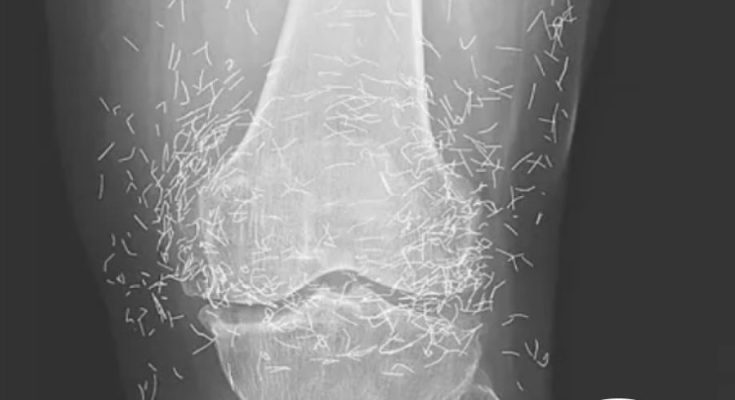

A routine X-ray revealed an unexpected surprise when doctors examined the knees of a 65-year-old woman suffering from severe joint pain. What they found was nothing short of astonishing — hundreds of tiny gold needles embedded deep in her tissue.

Acupuncture, a traditional therapy widely used in Asia, involves inserting thin needles into specific points on the body in an effort to relieve pain or treat illness. In this case, however, doctors say the gold needles were left behind intentionally as part of her treatment plan, designed to deliver continuous stimulation to the affected area.

There are other complications as well. Needles lodged in tissue can interfere with medical imaging. “They can obscure parts of the anatomy on an X-ray,” Guermazi noted. Even more alarming, patients with metal fragments in their bodies should never undergo an MRI, as the magnetic force could cause the needles to move — potentially puncturing blood vessels and causing life-threatening damage.

As for the South Korean woman, her case was recently documented in the New England Journal of Medicine. While the needles may have been intended to help, her X-rays tell a cautionary tale about the potential risks of extreme alternative therapies.